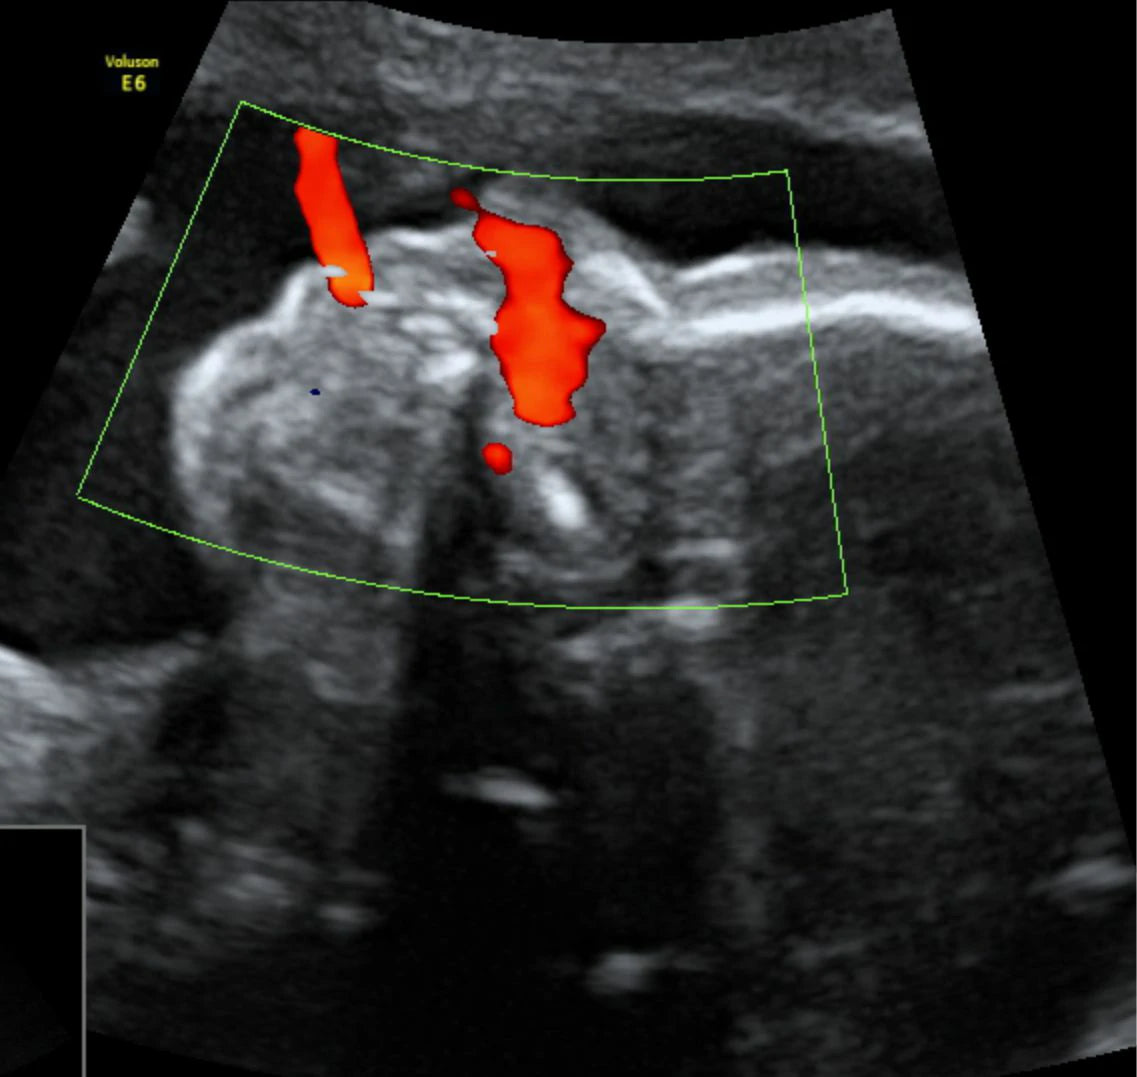

El perfil hemodinámico Doppler fetal es un estudio de ultrasonido especializado que utiliza la tecnología Doppler para evaluar la circulación sanguínea en el bebé y la placenta. Este examen permite a los médicos detectar posibles problemas de flujo sanguíneo y asegurar que el bebé reciba suficiente oxígeno y nutrientes a través de la placenta. Es una herramienta valiosa para monitorear el desarrollo y bienestar fetal, especialmente en embarazos de alto riesgo.

Imagen: Imagen de un perfil hemodinámico Doppler fetal mostrando la circulación sanguínea en el cordón umbilical y la placenta.